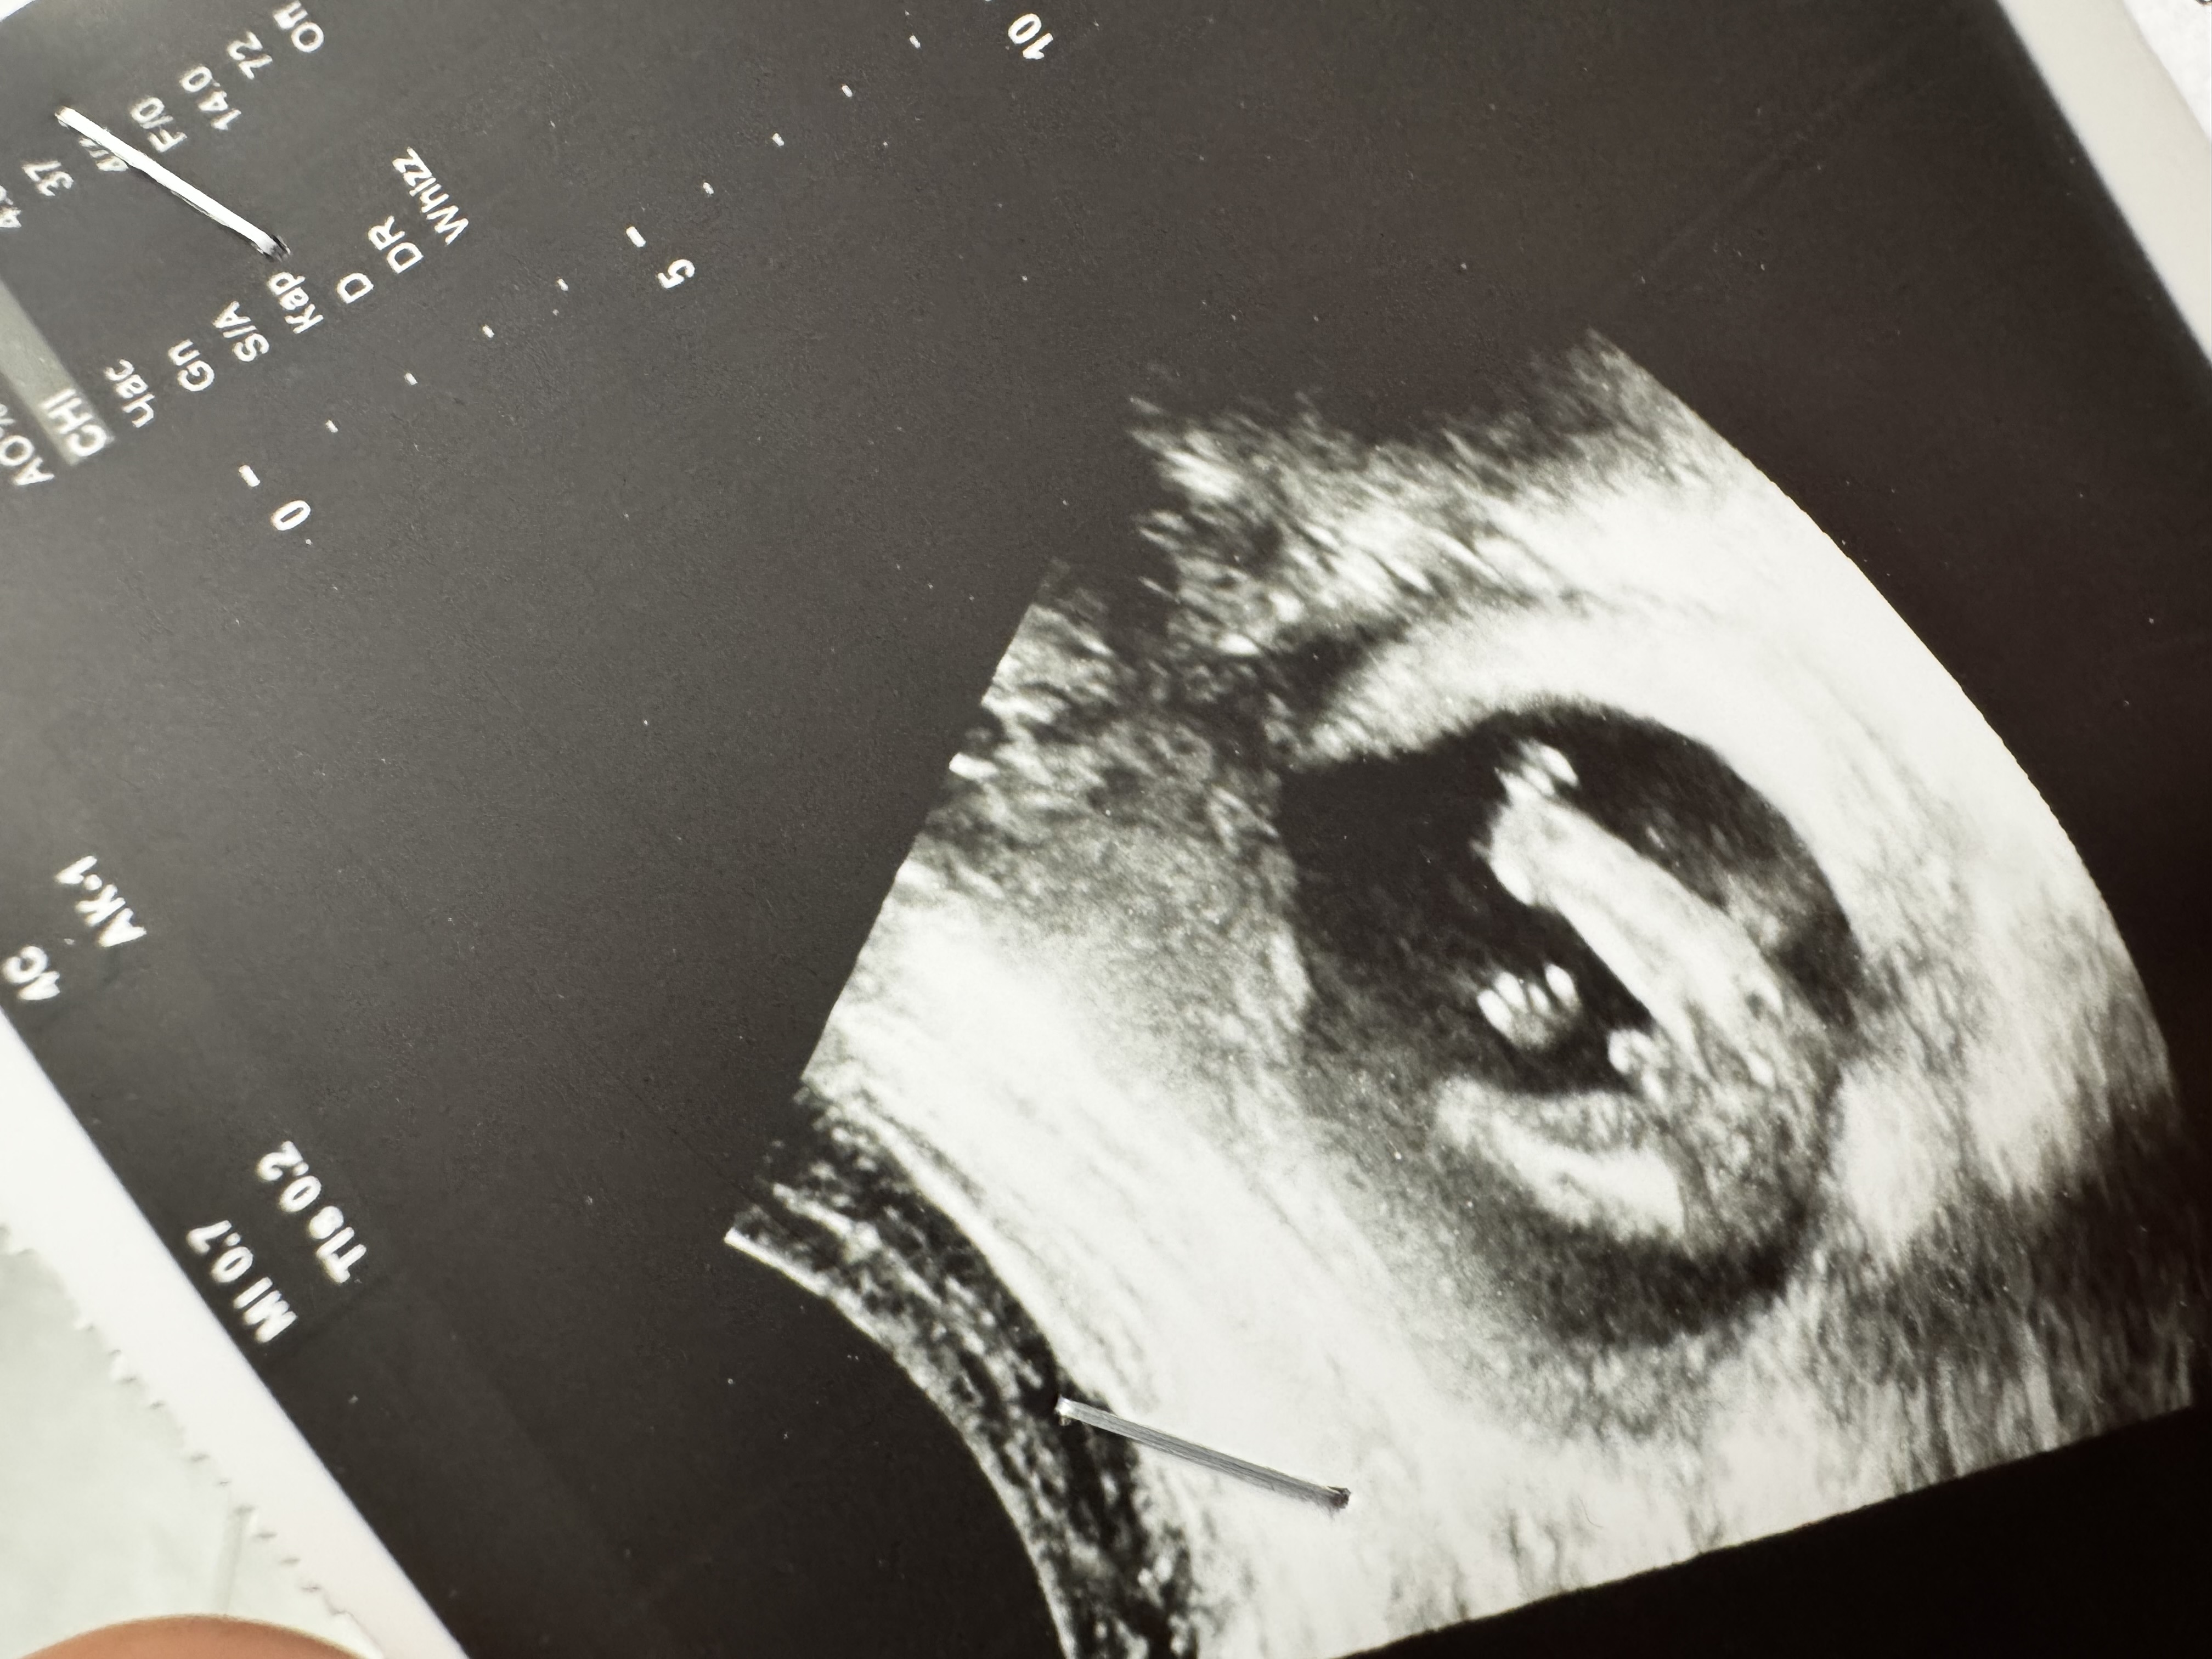

Елена в Благополучная беременность 10 месяцев Мальчик же? Пол малыша Я же все правильно поняла? (Вид попы снизу если что) Посмотрите еще 20 записей на эту тему Лучший ответ Маргарита без вариантов) сын) 26.02.2025 Ответить Отменить Ответить Чашка утреннего кофе Без сомнений мальчик)) 26.02.2025 Ответить Мама Лиля Ну тут даже без вариантов пацан. 26.02.2025 Ответить Tatiana Похоже на то 🩵 26.02.2025 Ответить Елена Думаю мальчик во всей своей красе 26.02.2025 Ответить Tanya Ага похоже на мальчика) Это узи на какой неделе сделано? 26.02.2025 Ответить Елена MamaTanya, 16+5, вроде как на этом сроке все уже должно быть понятно, не должно ничего исчезнуть) 26.02.2025 Ответить Tanya Елена, ну да, а врач пол не озвучил? Мне в 12 недель сказали пол, а в 16 подтвердили. Думаю, что у вас мальчуган будет ) поздравляю ❤️ 26.02.2025 Ответить Солнышко( БАНТИКИ,РЕЗИНОЧКИ) Скорее всего) 26.02.2025 Ответить Савва Похоже на то)) 26.02.2025 Ответить Пол ребенка по овуляции Пол Чаты Беременных Выберите чат: Январята-2026 Февралята-2026 Мартята-2026 Апрелята-2026 Майчата-2026 Июнята-2026 Июлята-2026 Августята-2026